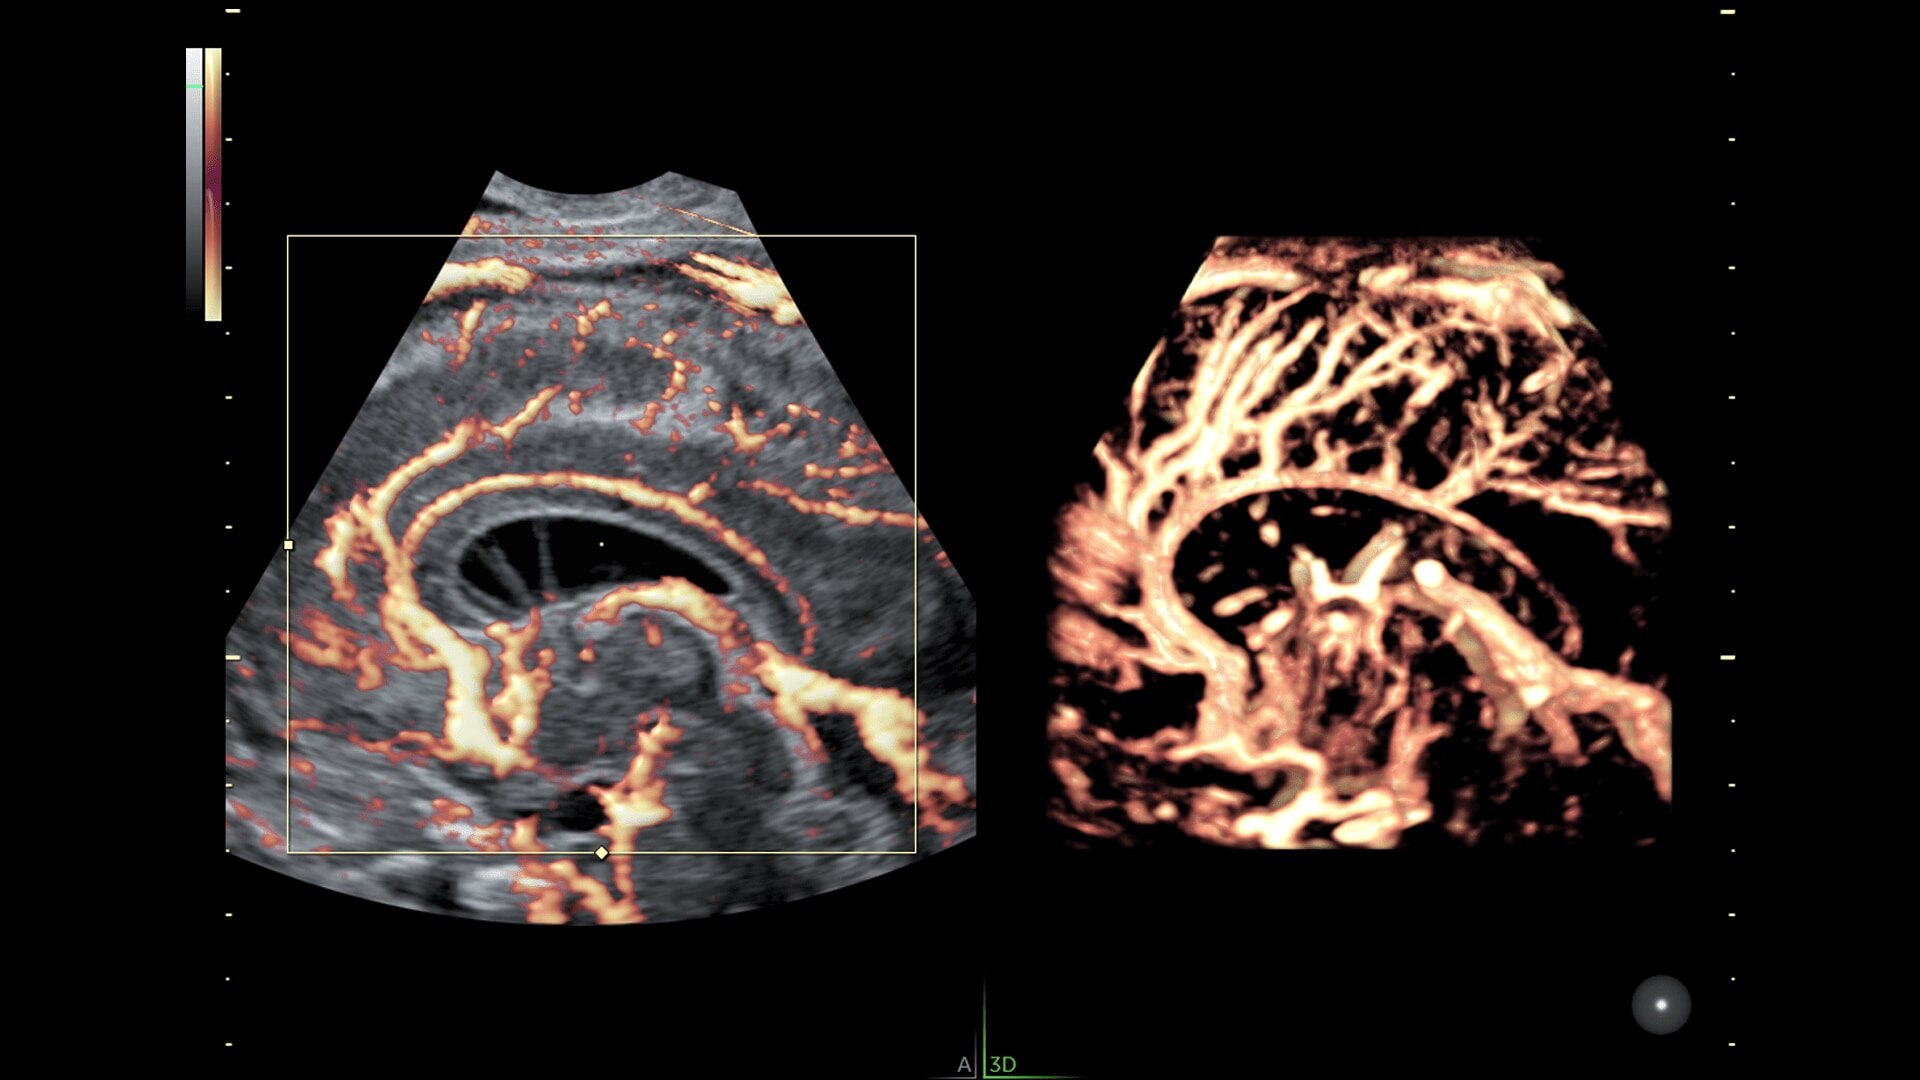

Graphicflow

Hemodynamic Visualization

Provides a graphical representation of the trajectories of the blood cells in real-time to visualize complex blood flow quickly and clearly, helping you to differentiate normal from abnormal hemodynamics